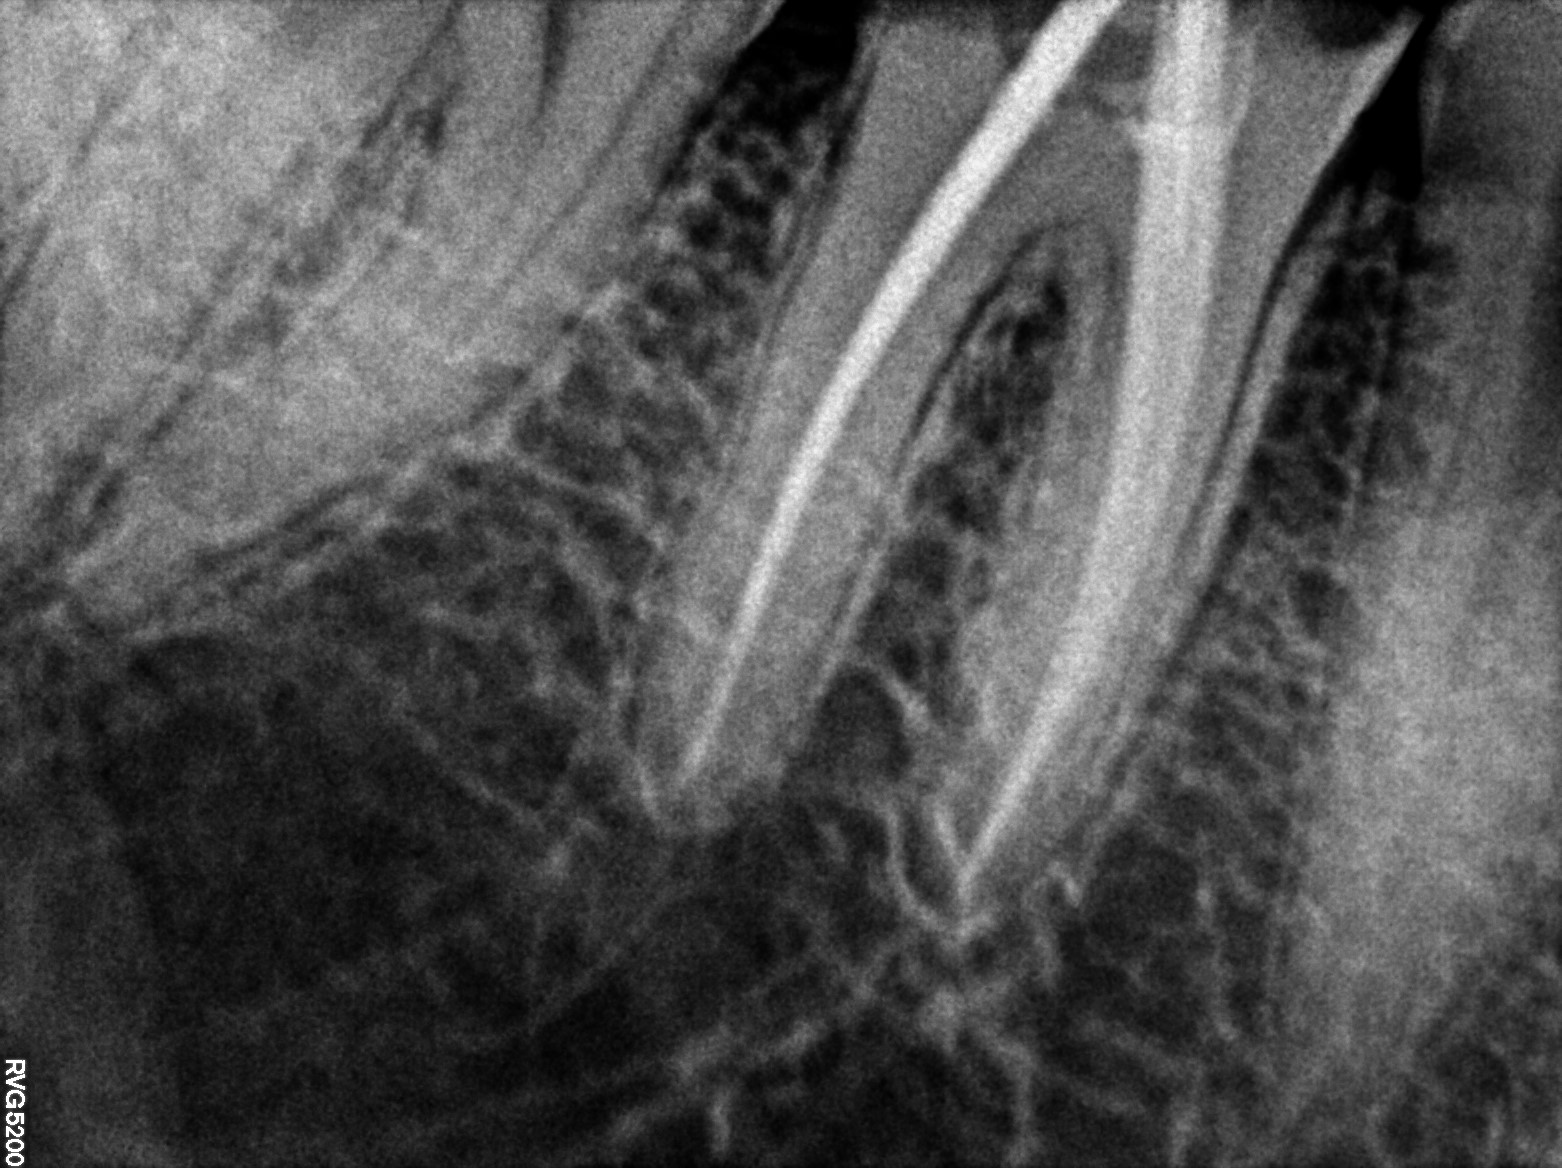

Dental Radiographs FHIR: DocumentReference · LOINC 24641-7

R5...5.jpg

24641-7